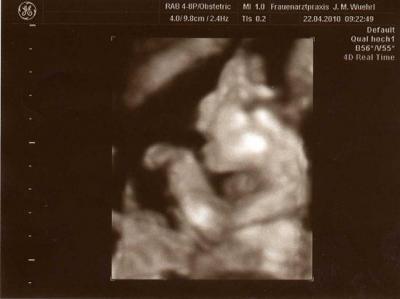

war heut beim fa weil ich so unterleibschmerzen und einen pilz eingefangen habe. dem kleinen gehts supi, ist schon etwas über 22 cm groß und SITZT im Becken, das ist auch der grund warum ich so schmerzen habe und dies kann auch sein, das das wehen auslöst die ich auch immer wieder habe. in 4 wochen will er schon mit dem ctg anfangen........ui ui ui wie die zeit vergeht....... :a042:

Bild zu war heut fa wegen schmerzen - Forum für September - Mamis

jaja was die kleinen so mit einem machenne :-) das Bild ich toootal Süß super getroffen LG Sandra